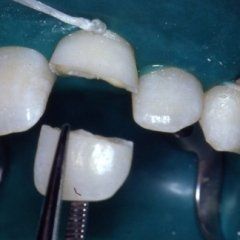

P3: Il trattamento endodontico si rende necessario quando la polpa del dente, comunemente chiamata dai Pazienti “nervo” è stata irrimediabilmente danneggiata da carie penetranti, fratture dentali, traumi o da cause imputabili a pratiche odontoiatriche scorrette. A volte la devitalizzazione del dente si rende necessaria, in corso di riabilitazioni protesiche complesse, per prevenire possibili problemi di ipersensibilità o per poter coinvolgere nel progetto terapeutico di recupero denti già di per se compromessi dal punto di vista parodontale. Presupposto per ottenere il successo in tale terapia è l’applicazione di un serio protocollo operativo che prevede tra l’altro l’uso di un telo di lattice, chiamato comunemente “diga”, che consenta la detersione e la pulizia dei canali del dente in un ambiente sterile e il controllo delle diverse fasi del trattamento attraverso delle radiografie endorali.